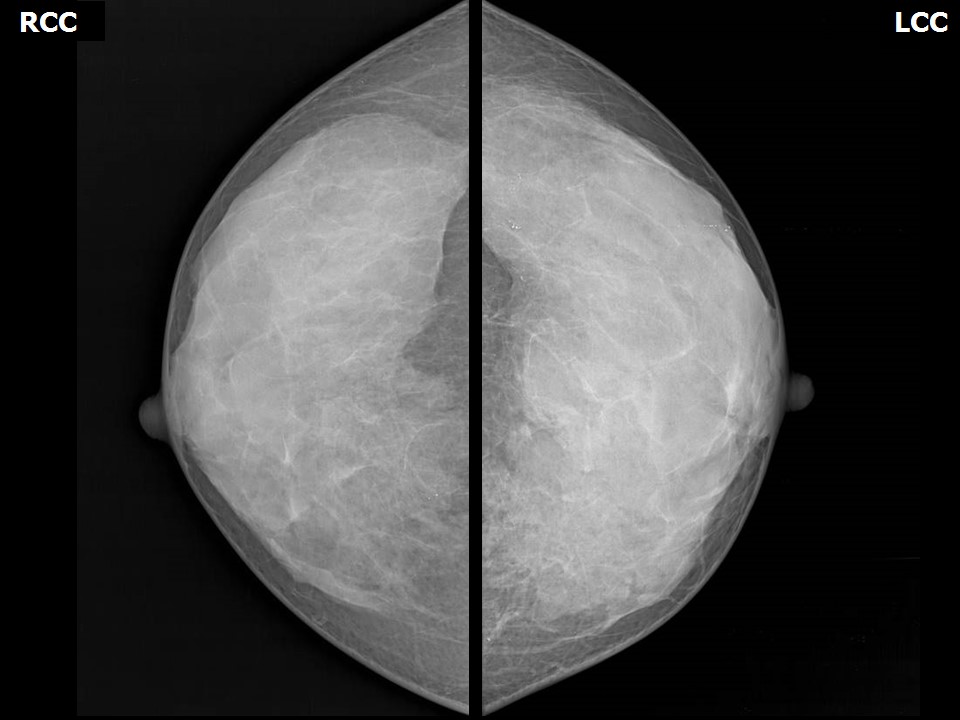

Феномен гипердиагностики в маммографии: примеры и иллюстрации

Раздел: Образы вокруг